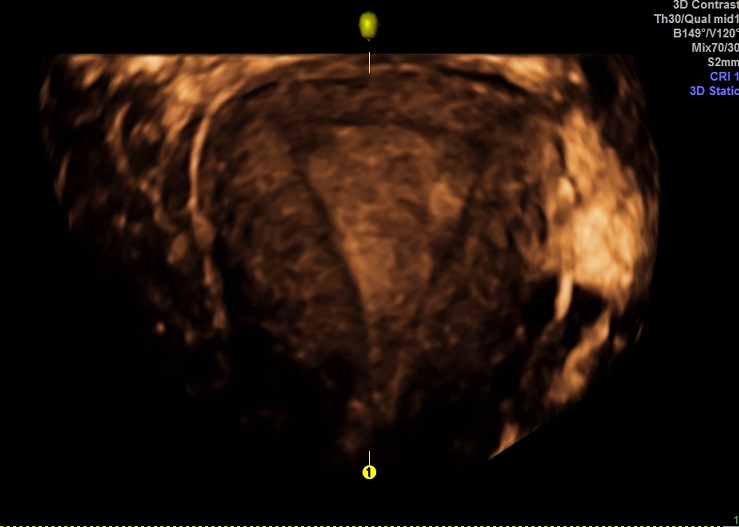

| 女性,25岁,继发性不孕1年余,难免流产4次。 | ||

2015-3-23 月经第19天检查 |

2015-3-23图示